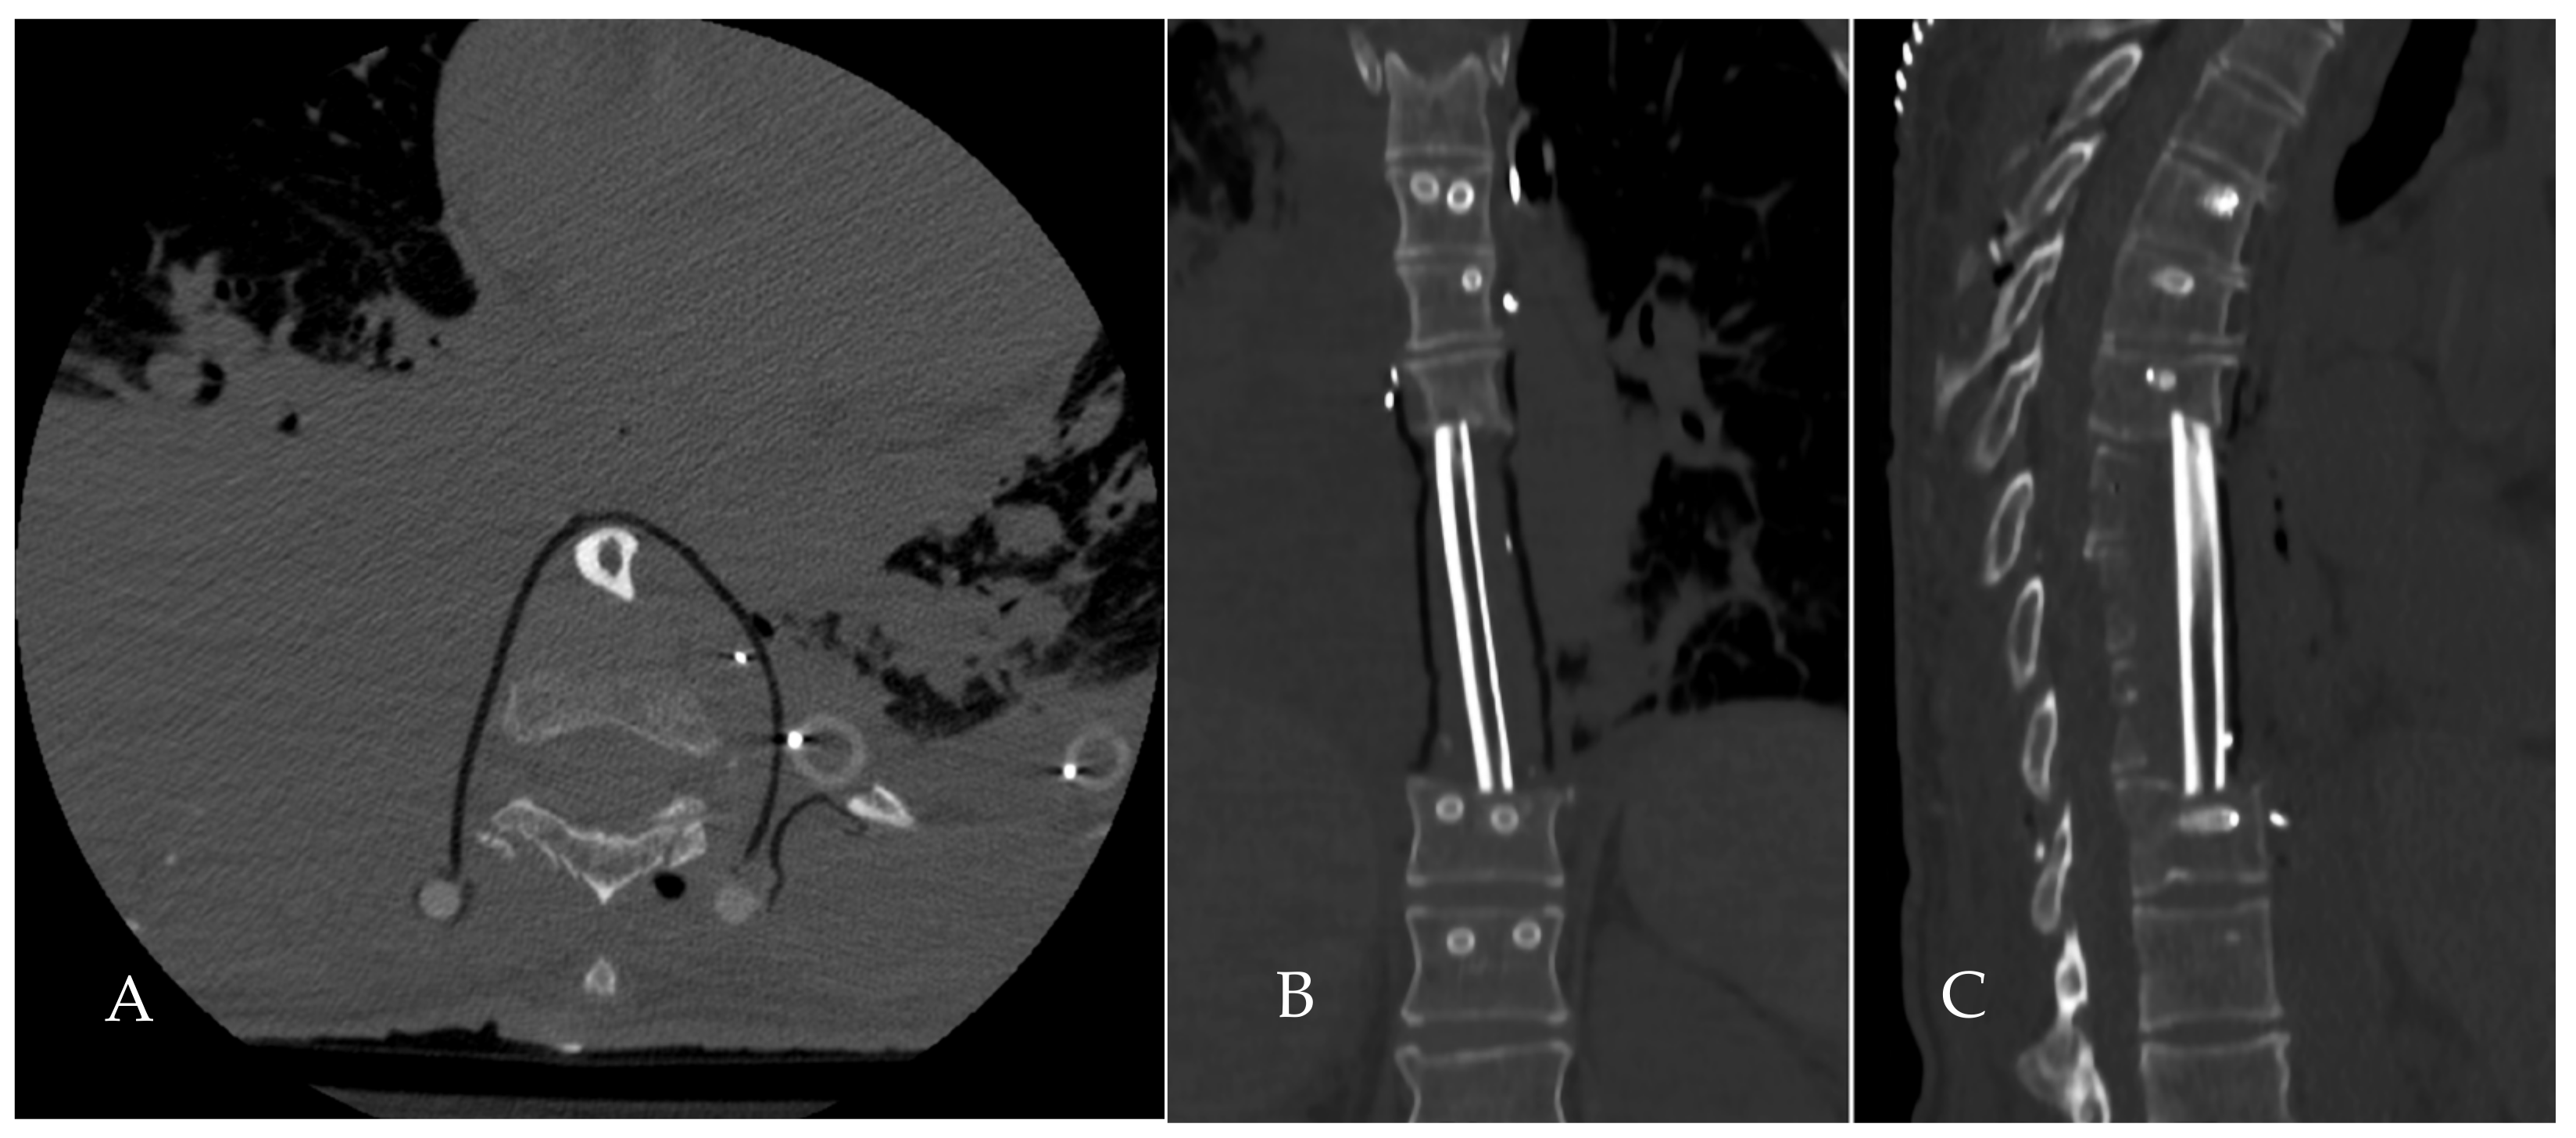

2.5. Reconstruction